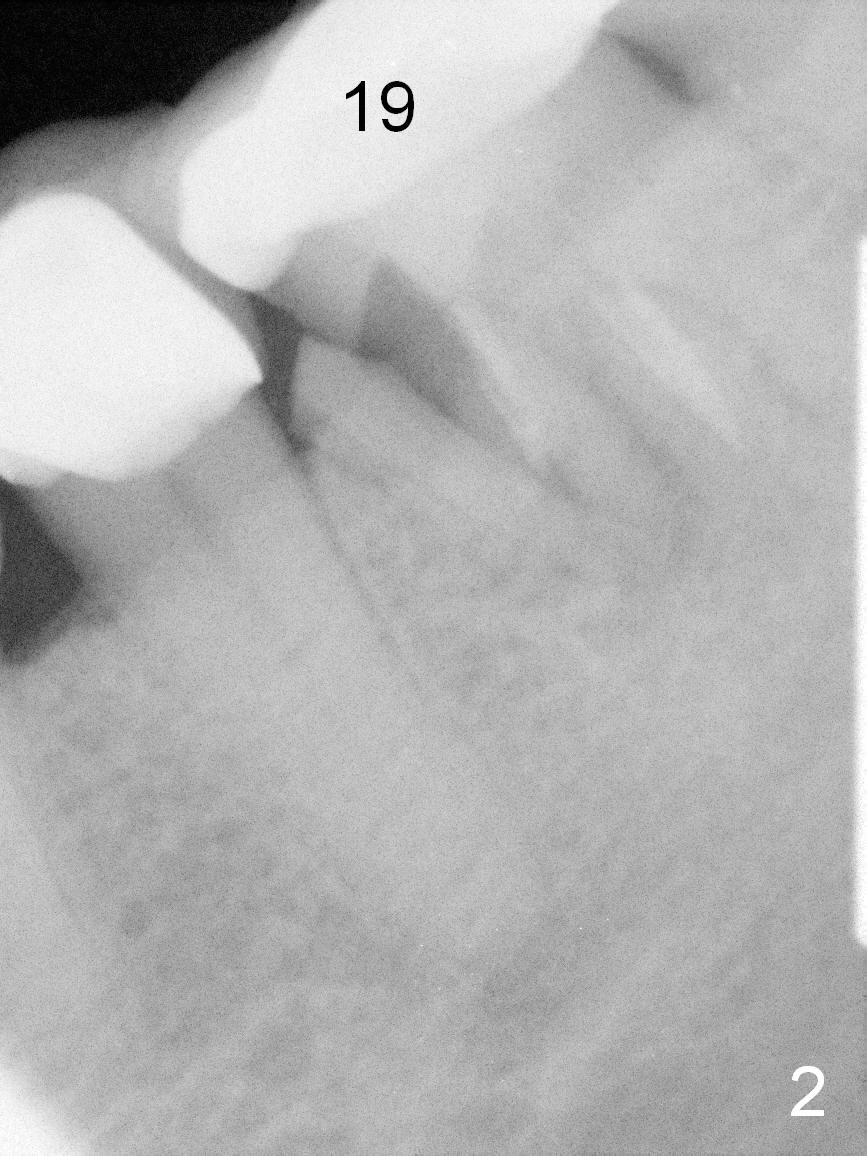

A 56-year-old lady (YW) has diabetes II, fairly well controlled. Although there is radiologic evidence of mesial root fracture of the tooth #19 (Fig.1 (panoramus)), she is asymptomatic. The buccal gingiva is slightly erythematous and edematous. There is no deep pocket. According to Fig.1, either the buccal or lingual wall is lost. This is not evident from Fig.2 (PA). Osteotomy is established in the septum or the distal socket (treated with Clindamycin), away from the lost plate (Fig.6,7). It is estimated that there is 4-5 mm apical bone. Measure the depth of the socket. Osteotomy should be 3 mm beyond the socket.